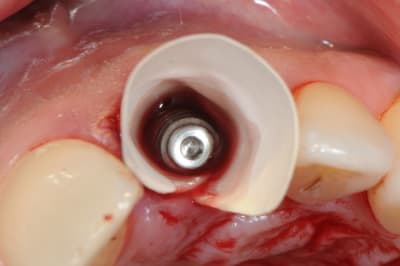

Une extraction avec mise en charge immédiate qui ne c'est pas bien passée (mauvaise ostéo-intégration), donc dépose (4x140mm) et repose d'un 4.6x140, et ROG car pas d'os vestibulaire.

Pas de camera alors juste quelques photos.

MP3 (OstéoBiol) et membrane évolution std 30x30mm (OstéoBiol)

Produit sympa qui ne laisse pas de particule comme le BioOss.

Pas de pin ou vis, seulement sutures.

Résultats dans 3 mois.